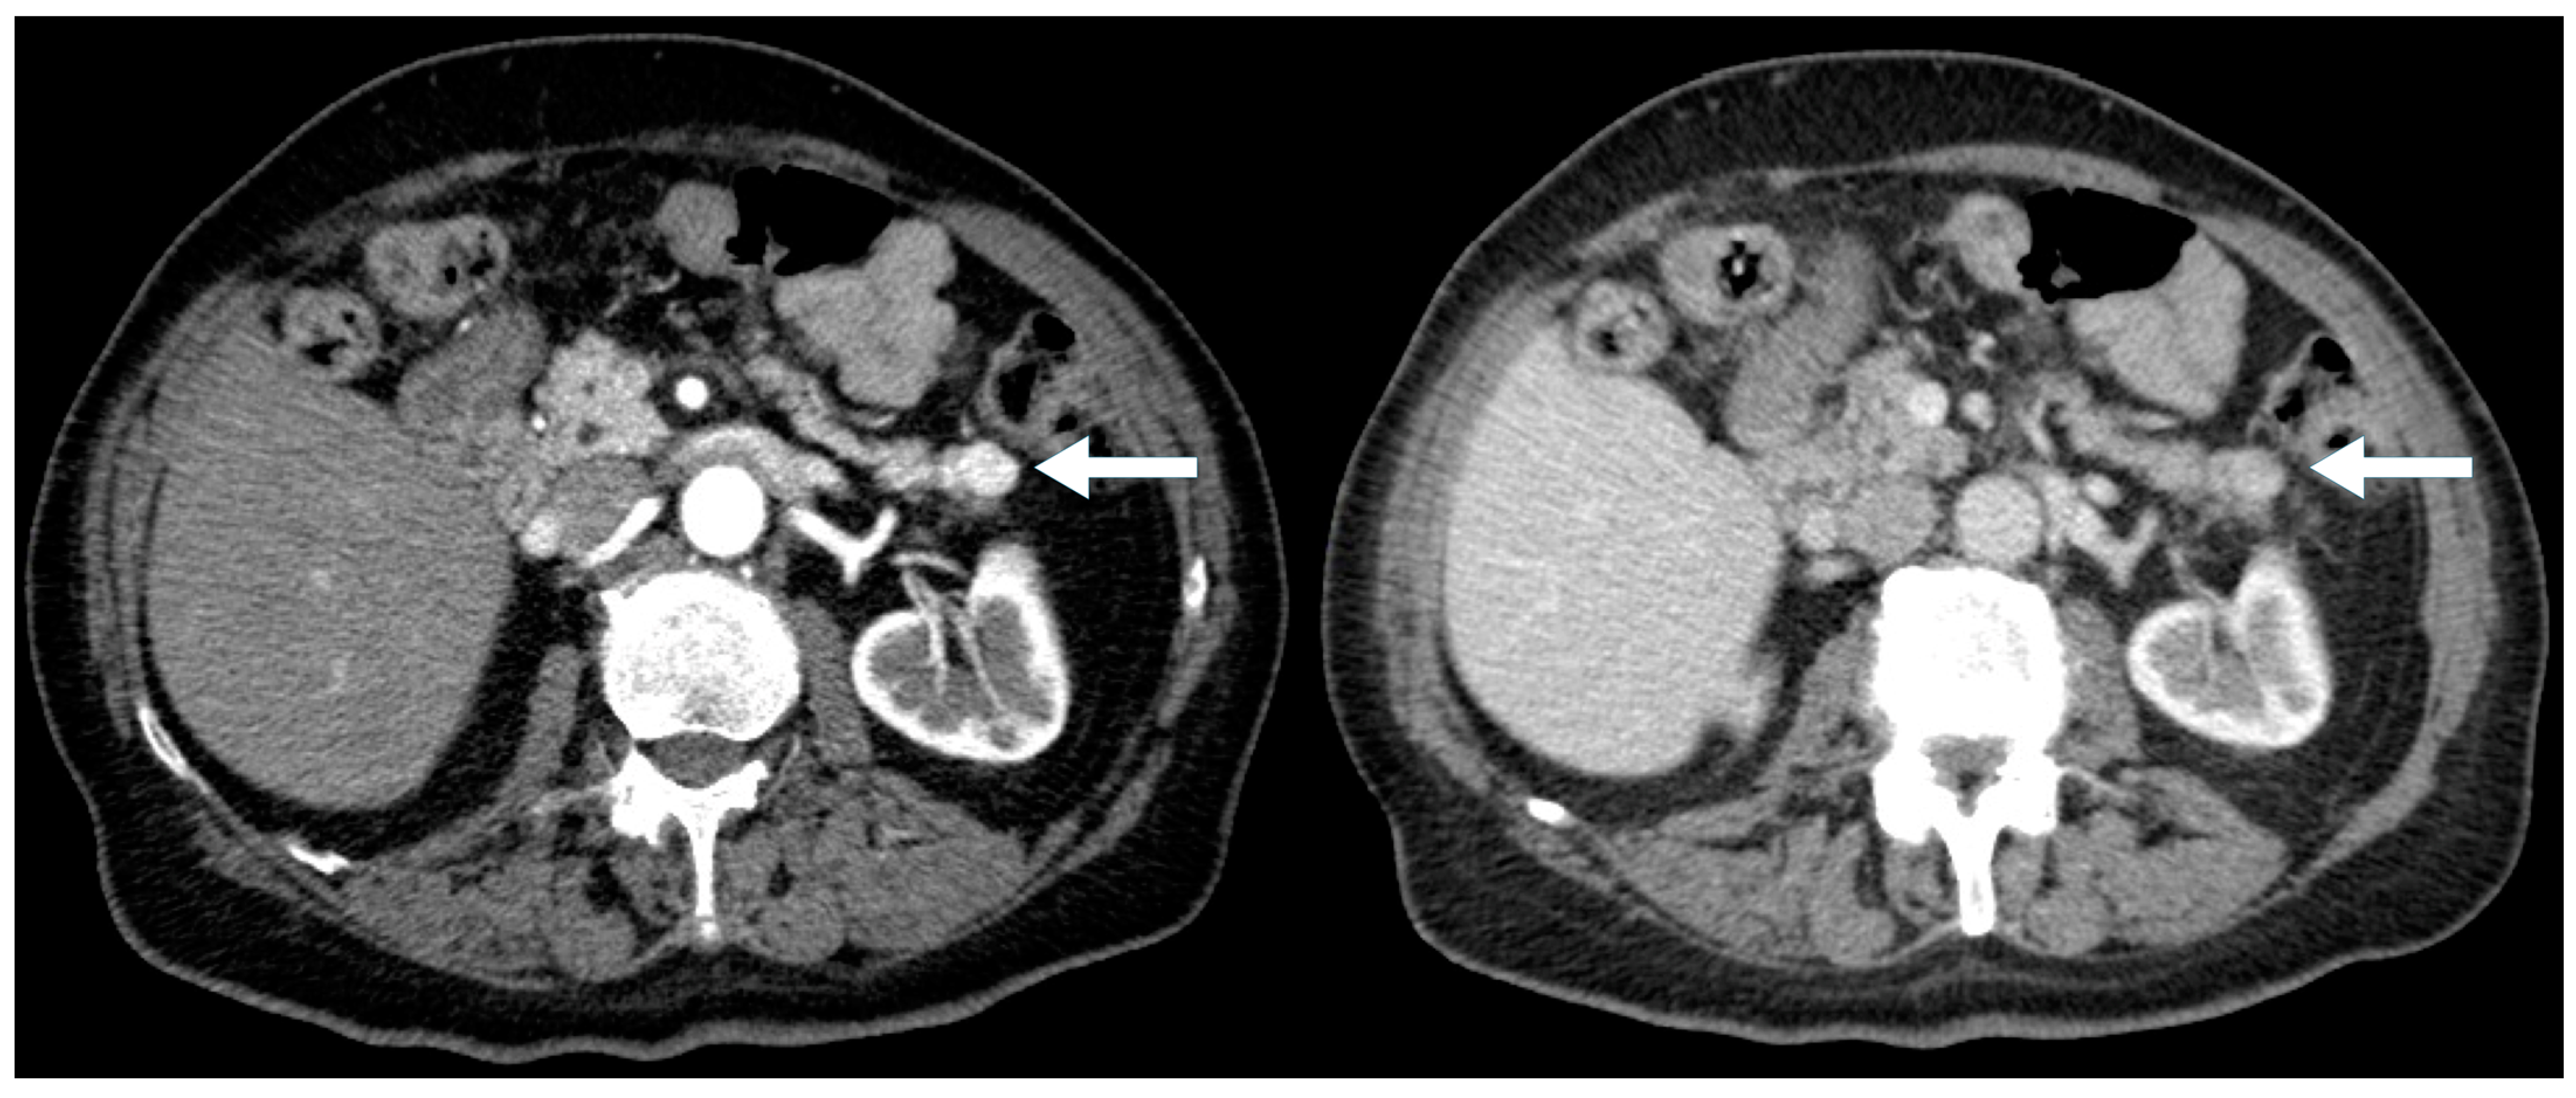

Symptomatic presentation was more frequent in the cystic PNENs (57% vs. 29% in the typical PNENs) (Figure 4 and Figure 5), and the lesions were larger (median size 2.5 cm vs. 1.7 cm). Calcifications and duct dilatation were also more common in the cystic PNENs (29% vs. 15% for calcifications and 14% vs. 10% for duct dilatation). Importantly, none of the cystic PNEN cases demonstrated locoregional invasion or metastatic disease.

Figure 4. A 56-year-old man presenting with painless jaundice. Contrast-enhanced CT demonstrates a pancreatic head mass (arrow) with mixed solid and cystic/necrotic components, showing arterial phase hyperenhancement. (left) Axial arterial phase CT. (right) Coronal arterial phase CT.